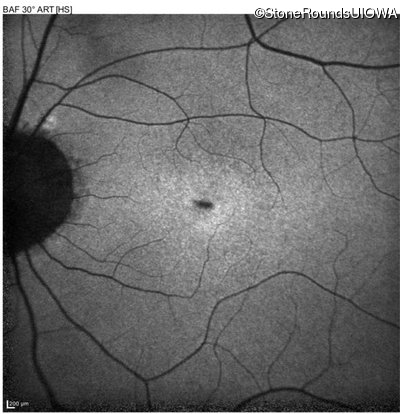

Blue Autofluorescence - Right - 20/40

Exemplar